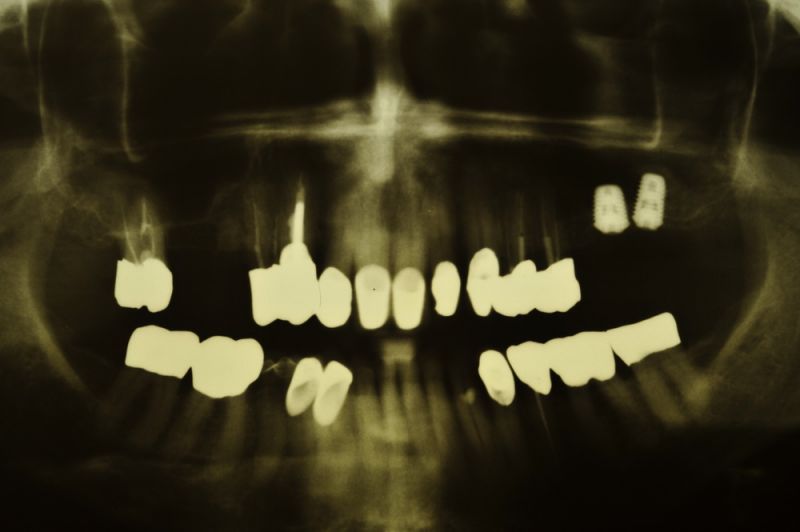

76 jährige Patientin mit 2 Implantaten und externem Sinuslift

Im Verlauf der Jahre ist es an verschiedenen Zähnen des Oberkieferseitenzahnbereichs zu Defekten und Beschwerden gekommen, die eine Entfernung mehrerer Seitenzähne nach sich gezogen hat und noch nach sich ziehen wird.

Am heutigen Tag sind in regio 26 und 27 zwei Implantate mit einem externen Sinuslift versorgt worden. Die Besonderheit des Eingriffs liegt darin, dass im Oberkieferseitenzahnbereich, bei einer noch vorhandenen Restknochenhöhe von wenigen Millimetern, zwei Implantate gesetzt und gleichzeitig eine Aufdoppelung des vorhandenen Restknochenangebots, durch die Schaffung eines Raumes zwischen knöcherner Abgrenzung der Kieferhöhle und der in die Kieferhöhle hinein verdrängten Kieferhöhlenmembran geschaffen werden konnte.